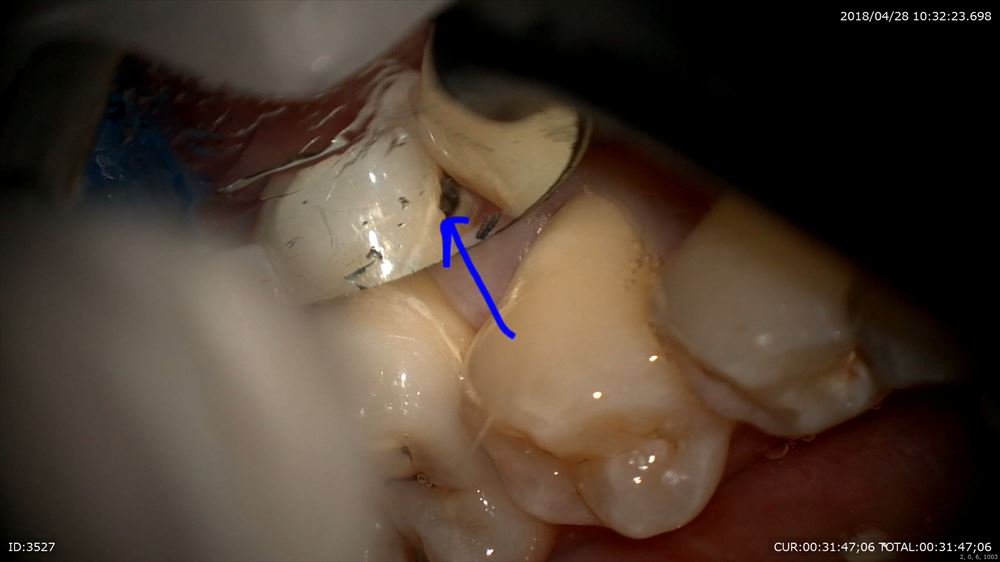

歯石の付きやすい(歯周ポケットの出来やすい部位)所。臼歯部遠心隅角。

はっきり見えますよね。

手指の感覚で、、、、、なんて必要ありません。